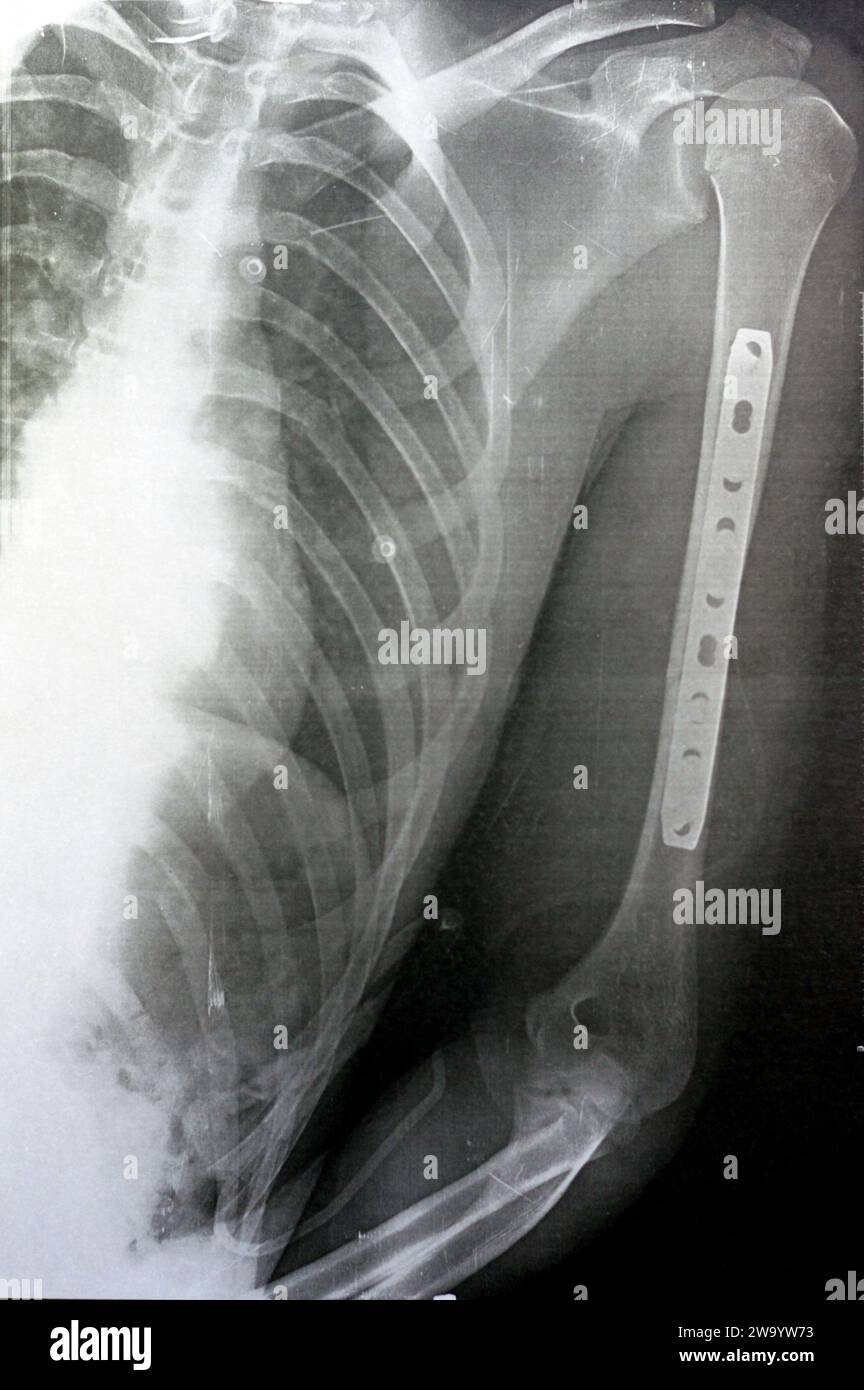

RF2WA30RC–Radiografia semplice che mostra frattura dell'omero sinistro dell'albero intermedio trasversale causata da un trauma diretto in un incidente stradale, gestito da riduzione aperta e fissa interna

RF2W9YW73–Radiografia semplice che mostra frattura dell'omero sinistro dell'albero intermedio trasversale causata da un trauma diretto in un incidente stradale, gestito da riduzione aperta e fissa interna

RF2WA2Y85–Radiografia semplice che mostra frattura dell'omero sinistro dell'albero intermedio trasversale causata da un trauma diretto in un incidente stradale, gestito da riduzione aperta e fissa interna

RF2W9YWMX–Radiografia semplice che mostra frattura dell'omero sinistro dell'albero intermedio trasversale causata da un trauma diretto in un incidente stradale, gestito da riduzione aperta e fissa interna

RF2W9YW6Y–Radiografia semplice che mostra frattura dell'omero sinistro dell'albero intermedio trasversale causata da un trauma diretto in un incidente stradale, gestito da riduzione aperta e fissa interna

RF2W9YWN6–Radiografia semplice che mostra frattura dell'omero sinistro dell'albero intermedio trasversale causata da un trauma diretto in un incidente stradale, gestito da riduzione aperta e fissa interna